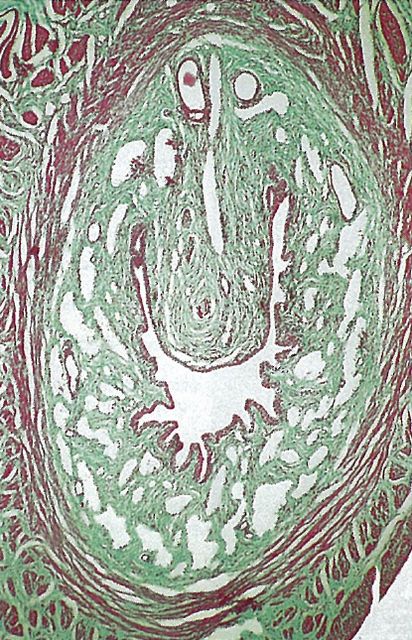

Рис. 19. Гистологическое строение бульбоуретральной железы

Рисунок 19 – Гистологическое строение бульбоуретральной железы